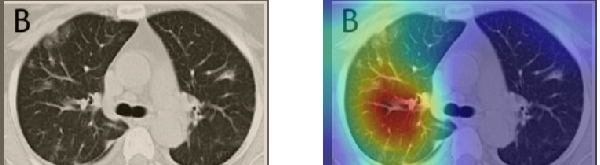

In order to make our models more transparent and provide detailed visual analysis, we present the Grad-CAM localization maps obtained by different models. We consider CT images with COVID-19 abnormalities from the test set of each dataset and highlight the important regions considered for the prediction. For the SARS-CoV-2 dataset we use the Inception V3 model. Figure 13 shows the original CT images and their localization maps. Our model is capable to detect regions that show abnormalities in the CT scans.

In a similar way, we consider classifying the test CT scans from the COVID-19 dataset by the DenseNet169 model and highlight the important regions considered for predictions. We present the original CT images and their localization maps in Figure 13. We can also see that our model is capable to detect the COVID-19 related regions as marked (small square in some images) by expert radiologists.

A wide variety of typical and atypical CT abnormalities have been reported for COVID-19 patients in various studies [58, 59]. So, we tested our models on external CT images extracted from these two publications as they feature typical findings of COVID-19 pneumonia marked by specialists. In order to make sure that not any of the extracted images are unintentionally included in our datasets, specifically the COVID19-CT dataset, we use the model trained on the SARS-CoV-2 dataset. First, the InceptionV3 model is employed to classify the extracted CT images. The model is able to correctly classify the given CT images as COVID-19. Second, in order to interpret the model’s generalization capabilities, we apply the Grad-CAM technique to visualize the regions of abnormalities that are considered. By assessing the different CT images in Figure 15, we can see that the model accurately localizes the disease-related regions. Even more interesting is the fact that the model ignores any specific marks in the images like letters and only localizes the COVID-19 related regions. These visual explanations show the success of our models to learn relevant, generic visual features related to COVID-19 and are capable to correctly classify CT images outside the datasets on which they are trained.